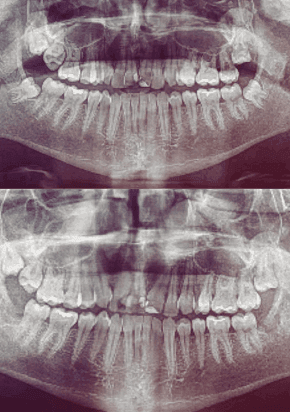

My mission is to offer excellence for you and your family, combining care, technology, and a truly human touch. I believe in individualized treatment, where each patient is unique and their needs are the priority. With an integrative approach, we look beyond the teeth to care for your overall health and well-being.